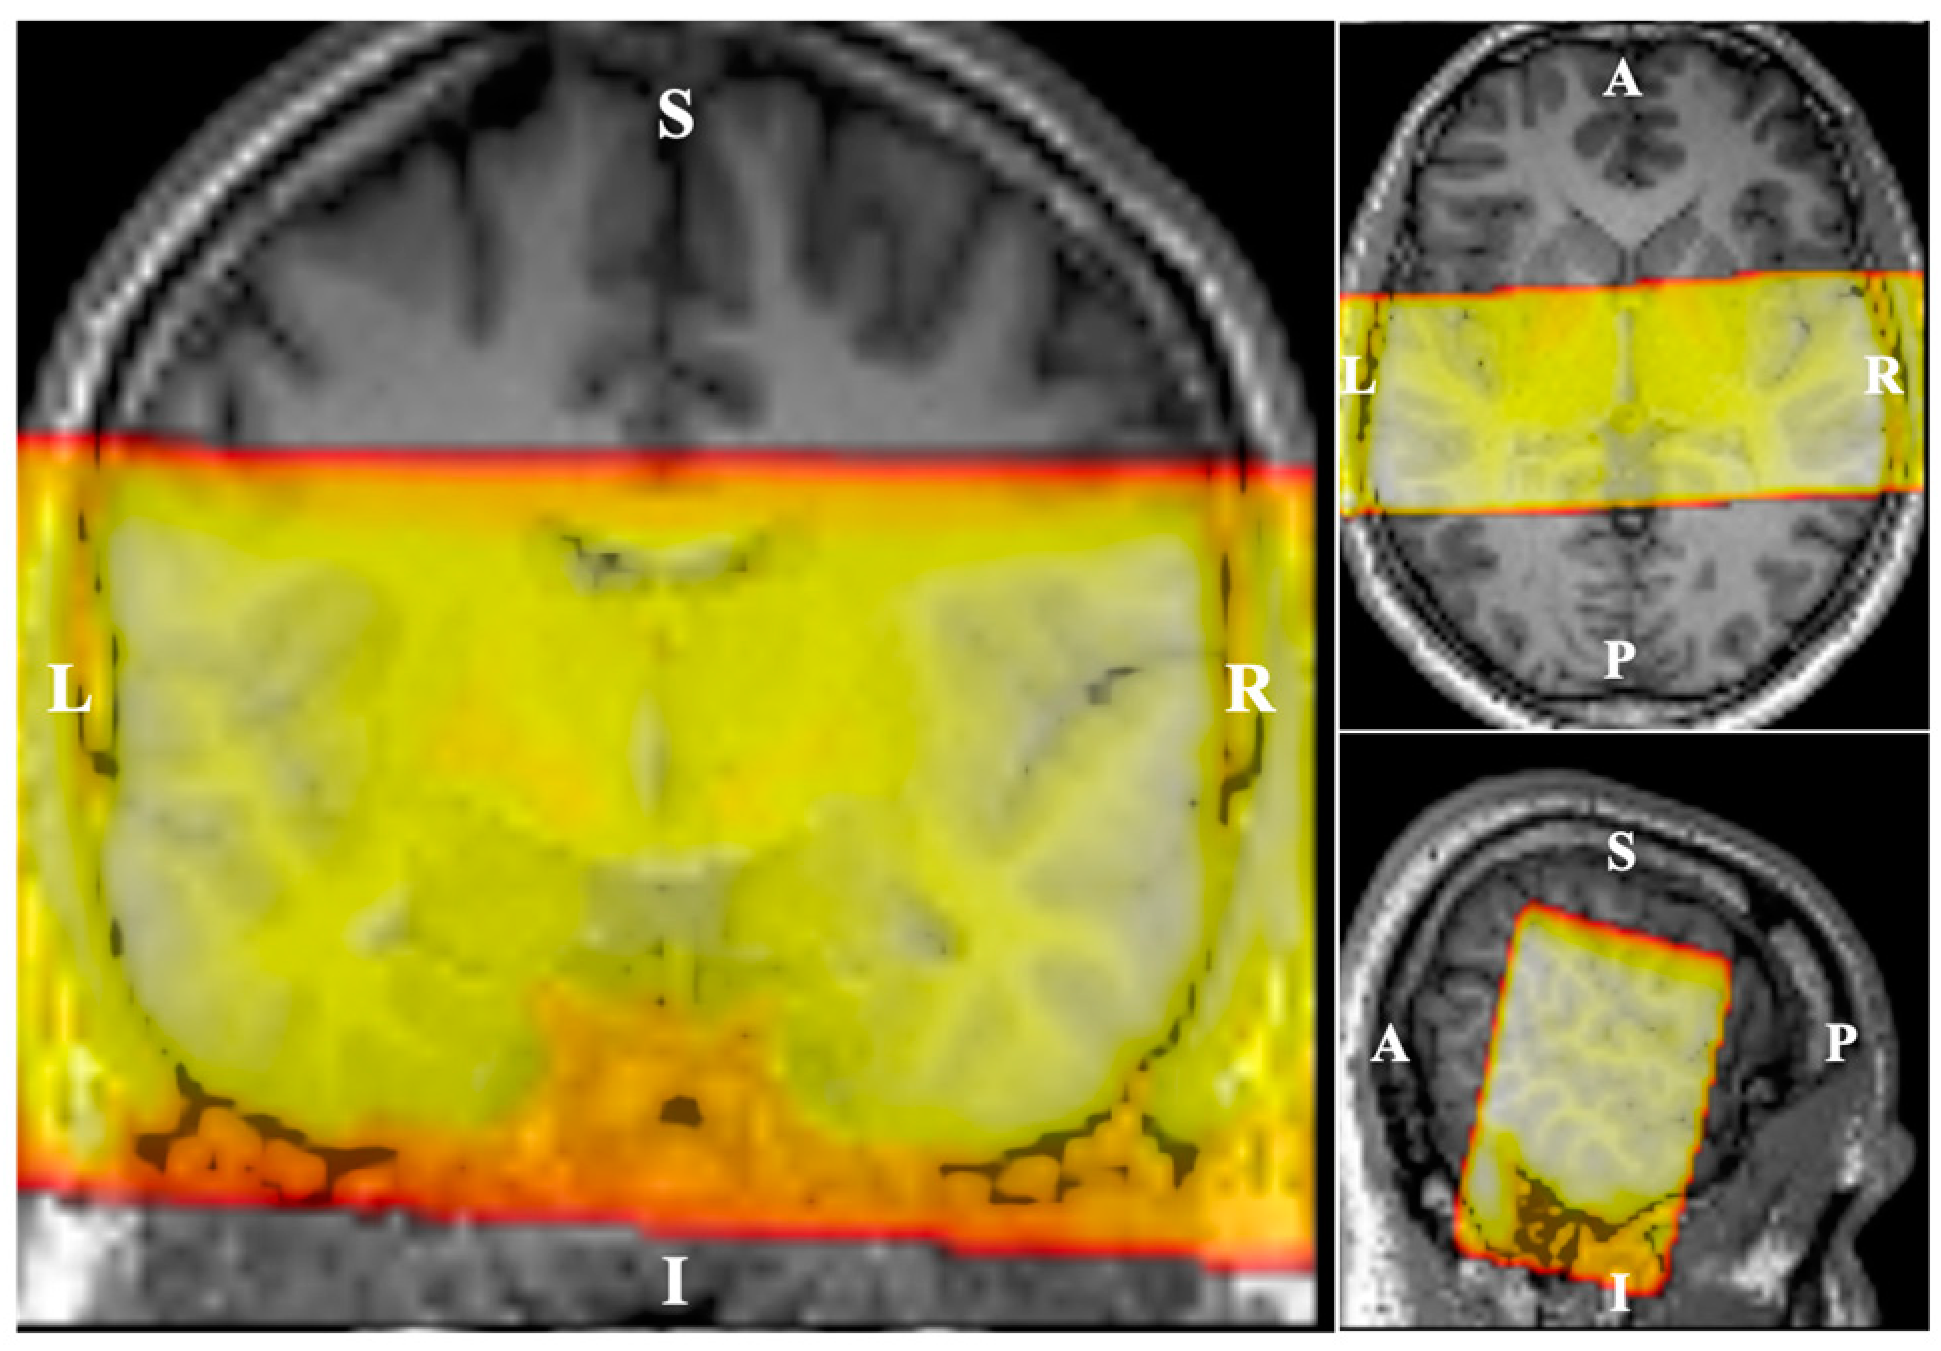

2.4.1. Pre-Processing